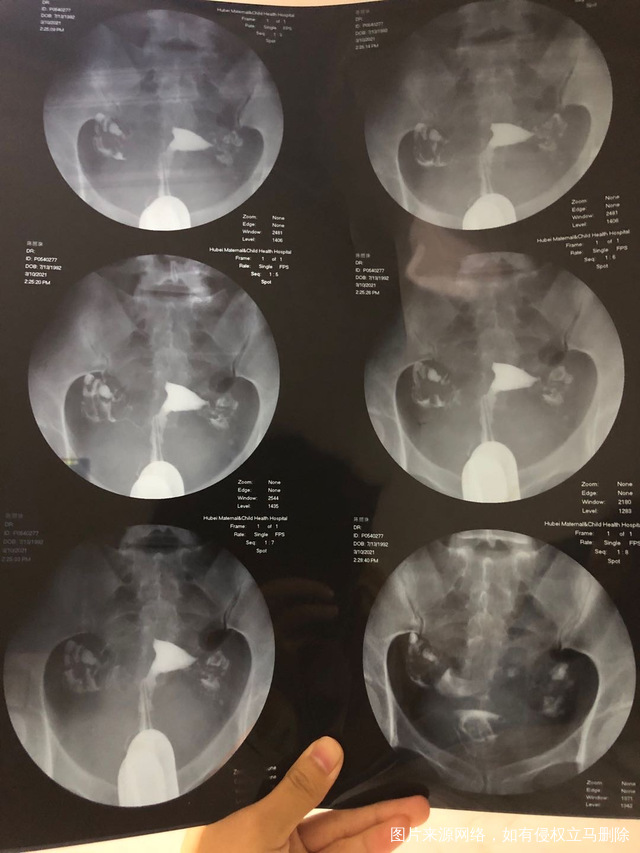

一子十岁隔年人流一次19年宫外孕保守治疗右侧